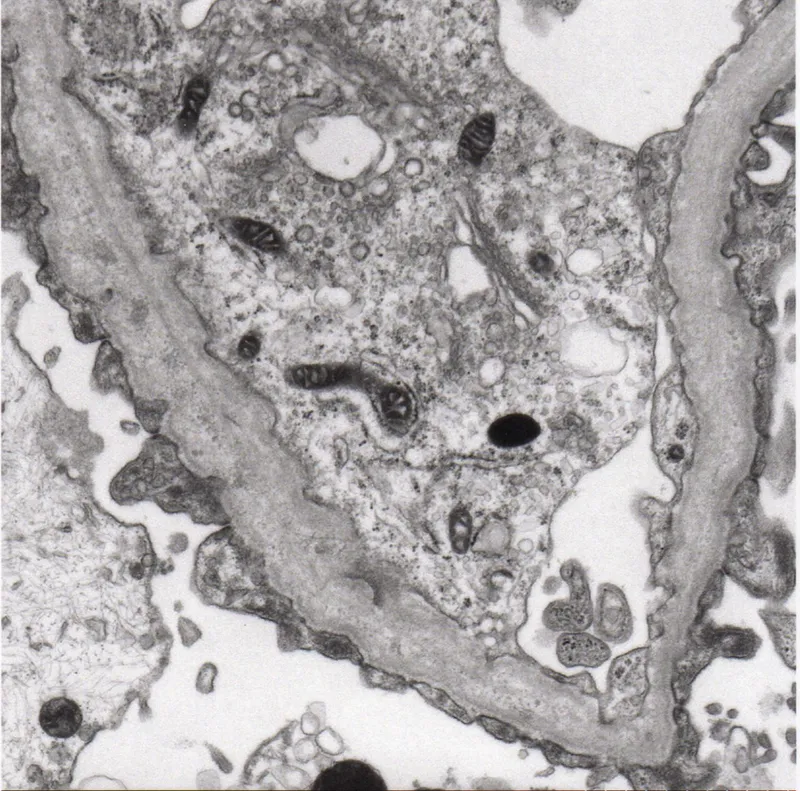

- Microscopy:

- LM: Diffusely hypercellular, proliferative glomeruli with neutrophils.

- IF: Granular, "starry sky" deposits of IgG and C3.

ā Classic finding: Subepithelial electron-dense deposits ("humps") on EM.